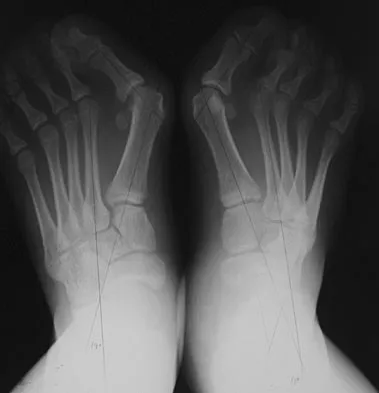

Question 58

A 61-year-old woman has increasing pain in her left great toe. She states that she has had discomfort for years but now has pain with all shoe wear. A radiograph is shown in Figure 35. To provide the most predictable pain-free result, treatment should consist of

Question 77High Yield